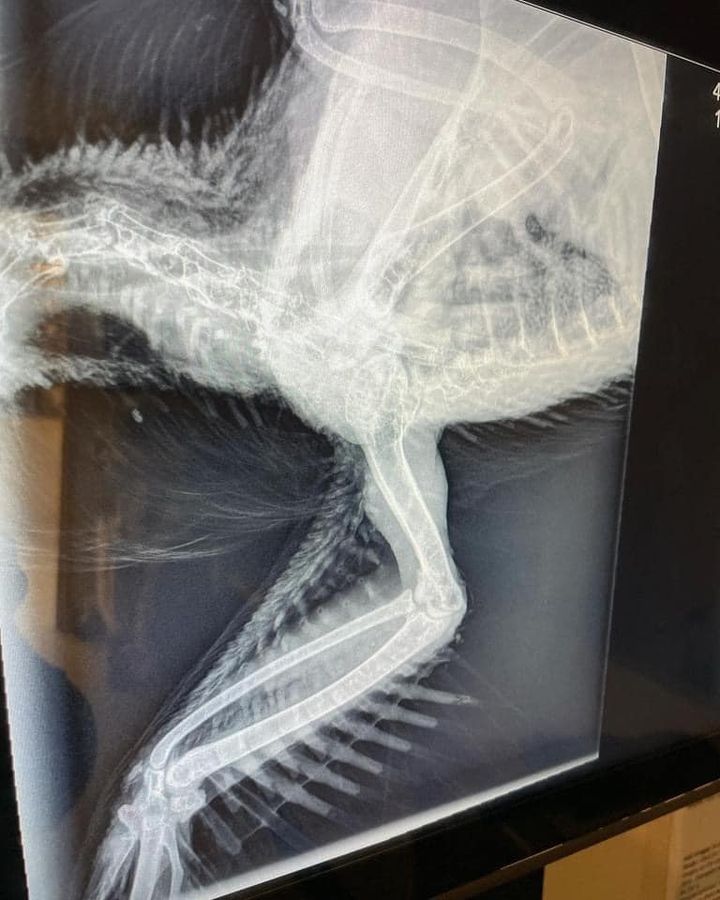

Leila, our little one eyed girl, has been isolated from the main flock for over six months. She had Trichomoniasis, a protozoal infection that causes lesions most commonly in the mouth and throat. It can be passed to other birds through sharing food and water and if not managed, can be fatal.

After several rounds of different medication and months of flushing and debridement of the cankers in her mouth, Leila has finally recovered and is happily spending time with the special needs crew where she can be closely monitored.